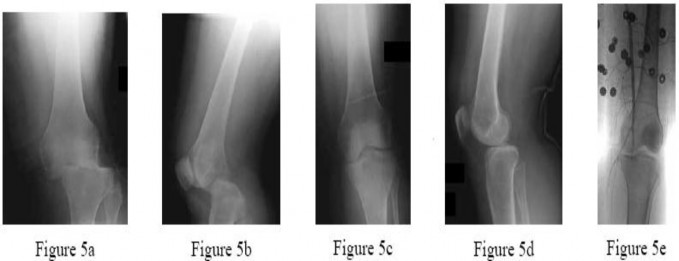

Question 30:

A 45-year-old male is struck by a vehicle and sustains a complex tibial plateau fracture. The injury is classified as a Schatzker Type IV fracture. What is the classic mechanism of injury, and which surgical approach is most commonly required for anatomic reduction and buttressing of this specific pattern?

Correct Answer: Varus force with axial loading; Posteromedial approach

Explanation:

Schatzker Type IV represents a medial tibial plateau fracture, classically caused by a high-energy varus force combined with axial loading. Because the medial plateau is dense and strong, this fracture implies high energy and often subluxation/dislocation of the knee joint. The optimal surgical approach involves buttressing the medial fragment, which is best achieved via a posteromedial approach to place an anti-glide or buttress plate.